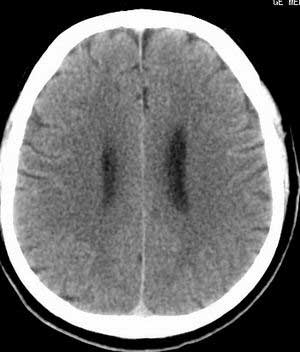

患者男,58岁。耳爆震伤后耳聋2年余,而后双耳道肿胀,间断性流脓。近一月来头痛、恶心、呕吐,右眼红痛,不能入眠。

在平扫时,见右侧枕骨下方小脑半球表面带状模糊稍高密度影,考虑为耳源性脑内感染。

脑实质密度均匀,未见异常密度灶,脑沟裂池室形态大小正常,中线结构居中.

双侧乳突蜂房密度呈气体样,慢性乳突炎可能性不大,

双侧颞叶脑实质密度均匀未见异常密度灶,

考虑颅内未见异常。

平扫右侧岩骨与枕骨交角内侧脑质内见淡片状密度增高影,内缘清晰。增强图象上未见明显显示。

考虑:1)伪影可能,建议复查头ct平扫。

2)加照头ct骨窗,以显示乳突气房内是否有病变。